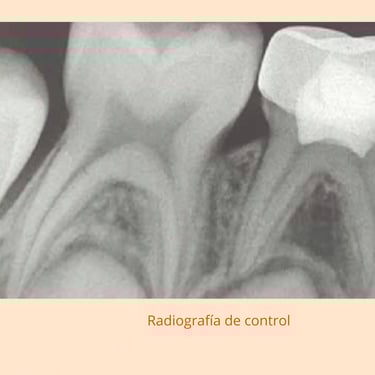

Evaluación Inicial: Examen visual y radiografías para identificar la necesidad de terapia pulpar.